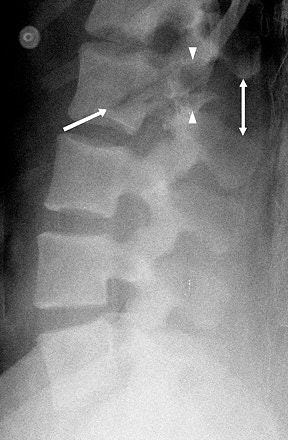

| Chance fracture in 28-year-old woman. Cross-table lateral radiograph of lumbar spine shows fanning of spinous processes (double-headed arrow) and fracture extending through pedicle (between arrowheads) and into L2 vertebral body (single-headed arrow). |